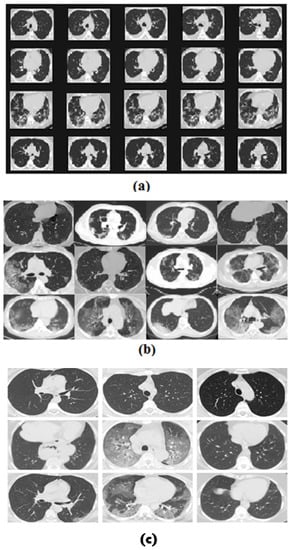

Figure 1a,b shows sample CT scan images of COVID-19 (+ve) and COVID-19 (-ve) patients from the mentioned dataset.

Figure 1. Sample images taken from (a) SARS-CoV-2 CT scan dataset, (b) COVID-CT database images that are positive for COVID-19, and (c) COVID-CT database images that are negative for COVID-19.